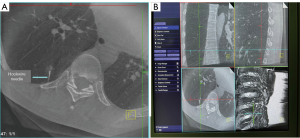

After general anesthesia and double-lumen tracheal intubation in the operating room, the patient was placed in the left lateral decubitus position, and a metal fence needle was placed on the patient’s skin surface for marking. As the patient’s breath was held with the assistance of an anesthesiologist, we acquired CT images of the patient’s initial spin scan using the high-quality image acquisition protocol of the Cios Spin system (Siemens Healthineers AG, Erlangen, Germany; Figure 3A). In addition to the preoperative planning of the puncture positioning path and the initial CT image, we determined the needle entry point and used the hookwire needle to puncture the patient’s lung (Figure 3B). We acquired CT images of the patient once more using the Cios Spin system. The CT image revealed that the hookwire was accurately placed next to the GGN in the patient’s right lower lung and that there was no pneumothorax or hemothorax (Figure 4). The entire positioning process took 25 min.

This case study explored a complete one-stop pulmonary nodule localization and VATS lung resection procedure. First, we performed 3D reconstruction of the patient’s lung using the patient’s conventional CT imaging data and through Mimics software (version 20.0; Materialise, Leuven, Belgium) before performing puncture localization. We used 3D lung reconstruction to plan the optimal puncture positioning path for the patient. We then selected the shortest possible puncture line while avoiding important vessels and tissues. Moreover, in the event of puncture and positioning failure, we had an alternative surgical plan, namely VATS segmentectomy based on lung 3D reconstruction technology. Second, to reduce the number of scans and radiation exposure, before starting, we moved the C-arm to a suitable rotational scanning position through the built-in laser positioning line and a 2D image of the Cios Spin system and adjusted the operating table, patient position, and C-arm position through the prerotation function to avoid collisions. Furthermore, to obtain clear and reliable CT images and reduce artifacts, we used the high-quality image acquisition protocol of the mobile 3D C-arm system and after the patient was anesthetized, the anesthesiologist gave the patient positive pressure ventilation to keep the lungs inflated.